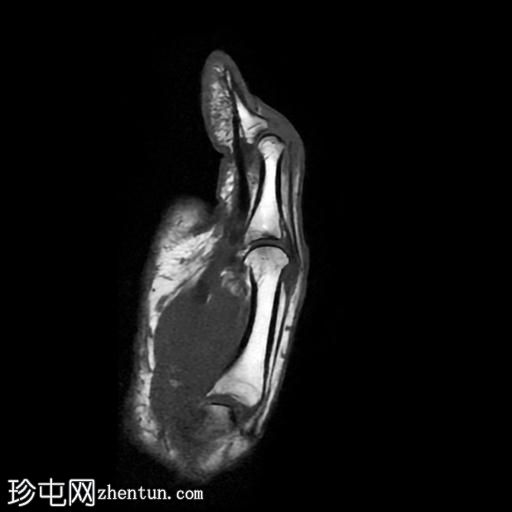

矢状位

T1加权像

拇指长伸肌腱远端近乎完全撕裂,撕裂部位位于指间关节和远节指骨基底部,伴有拇指屈曲畸形。

近端撕裂端位于近节指骨颈部附近,撕裂端之间约有9毫米的间隙。

拇指近节指骨基底部以及第一掌骨头颈部可见骨髓水肿。

此外,第一掌指关节水平的尺侧副韧带显示异常的实质内液体信号增高和增厚,与尺侧副韧带扭伤有关。

MRI 结果提示拇长伸肌腱近乎完全撕裂,并伴有拇指屈曲畸形。